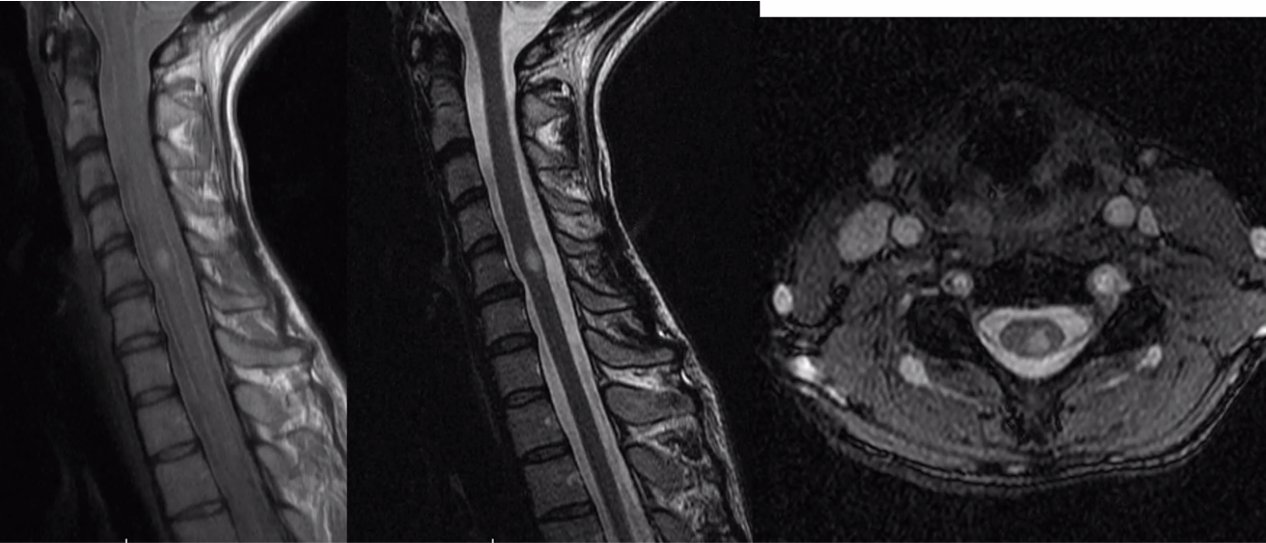

Spinal DAVF will have no flow voids in the cord itself, with have funky serpentine vessels surrounding the cord

spinal avm

notice the flow voids in the spiral cord. Spinal DAVF will have no flow voids in the cord itself, with have funky serpentine vessels surrounding the cord

MS in the spine

ependymoma would be CENTRAL